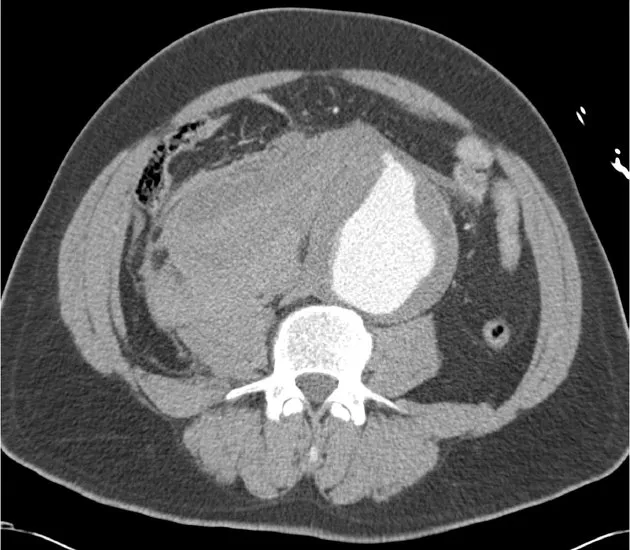

Ruptured Abdominal Aortic Aneurysm (AAA):

- Aorta diameter > 3 cm; rupture risk ↑ if > 5.5 cm.

- CTA Signs of Rupture:

- Retroperitoneal hematoma (most common).

- Active contrast extravasation.

- Draped aorta sign.